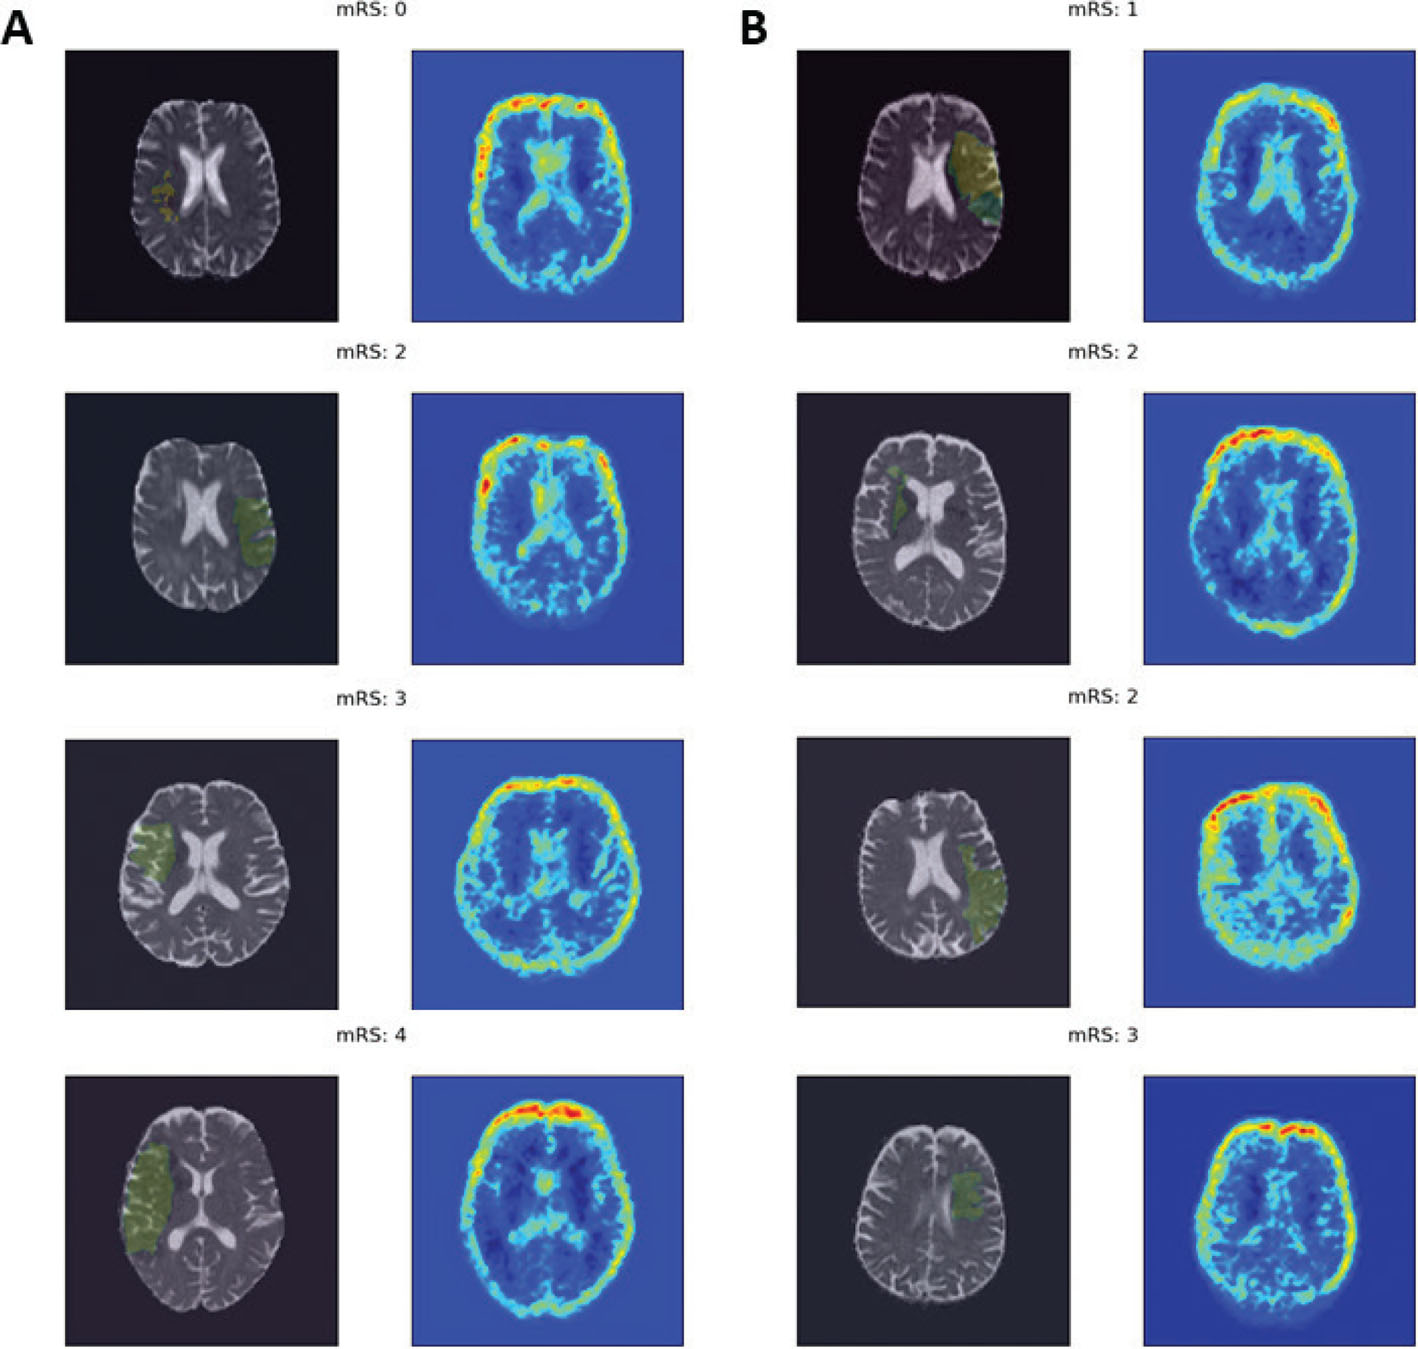

A feature importance explanation method that is specifically designed for imaging-based CNN models and can provide local explanations is Gradient-weighted Class Activation Mapping (Grad-CAM) (39). Grad-CAM calculates the rate of change in the prediction of a target class regarding a change in the input features (i.e., pixel/voxels). By allowing the preservation of spatial information, Grad-CAM identifies regions of interest in the input image that are important for the prediction rather than individual pixel/voxels. These regions of interest can be then visualized as heat maps allowing for qualitative analysis of the important areas through visual inspection. We applied Grad-CAM on a CNN model that was trained on MRI Apparent Diffusion Coefficient (ADC) maps of 40 hyperacute ischemic stroke patients to predict 90-days mRS (AUC:0.91) (40). Figure 4 shows the heatmaps generated from the quantitative Grad-CAM analysis for eight example patients, all classified correctly by the model. The heatmaps showed that the model did not focus on the visible ischemic regions in the ADC maps but consistently focused on the boundaries of the brain. This may suggest that the model’s predictions were likely based on MR artefacts rather than pathophysiological information represented in the ischemic regions of ADC maps. On the other hand, by focusing on the boundaries, the model may have discovered atrophy related to the patient’s age. These results highlight that (i) high performing models are not necessarily reliable, and (ii) when the explanations do not identify imaging features that are known to be predictive of functional outcome, it is hard to determine why.

Fig 4

Figure 4. Activation maps. Illustration of class activation maps for correctly predicted patients from the A, training, and B, validation data. For each patient, a slice from the ADC (apparent diffusion coefficient) maps is shown with the lesion mask overlayed. The generated heatmap for that slice is shown beside the original image, where red and yellow areas indicate regions of interest.

A global understanding of the model’s decisions can highlight possible confounding factors or inappropriate features that may have driven the decision. For example, our study using ADC maps (40) to predict functional outcome demonstrated that a high performing model, contrary to expectations, may have focused on imaging artefacts, or factors related to age, instead of the ischemic region. The use of xAI tools can help prevent a phenomenon like this while the model is still in the development phase, i.e., before it is adopted in another hospital setting, allowing a medical expert to detect and correct misguided decisions.